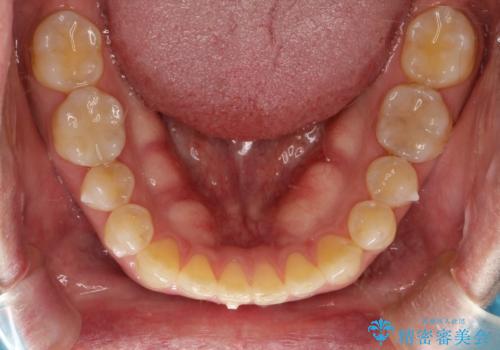

- 上顎の正中の隙間が気になるとのことで来院されました。

下の歯と歯の間をわずかに削り、スペースを作り、正中の隙間を閉じる計画としました。

装置はインビザラインにて行いました。

インビザラインで目立たずに矯正治療を行うことができました。

使用時間を守っていただけたので、比較的スムーズに矯正を終了することができました。